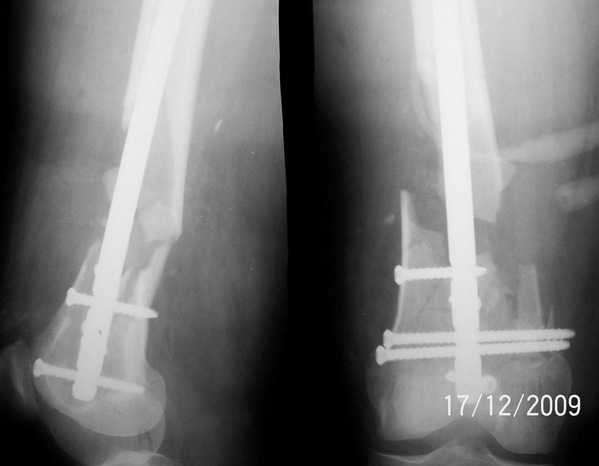

1. Открытый с дефектом кости 5 см оскольчатый внутрисуставной перелом дистального эпиметафиза бедренной кости. Величина дефекта установлена после сравнительных рентгенограмм обоих бёдер с линейкой. При поступлении выполнена ПХО раны, скелетное вытяжение за бугристость большеберцовой кости.

2. После долгих сомнений выполнена открытая репозиция перелома эпифиза бедренной кости, закрытый блокированный интрамедуллярный остеосинтез (к слову, оперативное вмешательство выполнено без применения ЭОПа). Предполагалась через 8 недель пластика костного дефекта спонгиозным аутотрансплантатом.

3. Снимок через 10 недель после операции. Имеется облаковидный регенерат. Решено от костной пластики воздержаться.

4. Через 6 месяцев имеем сросшийся перелом.

Безусловно, так бывает не всегда. Но, что касается показаний к костной пластике, такой вариант развития событий надо иметь ввиду.